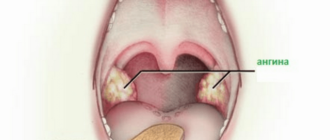

Давит в области горла

Невропатолог

Почему возникает ощущение сдавленности в горле Ощущение сдавленности в горле присутствует при многих состояниях.